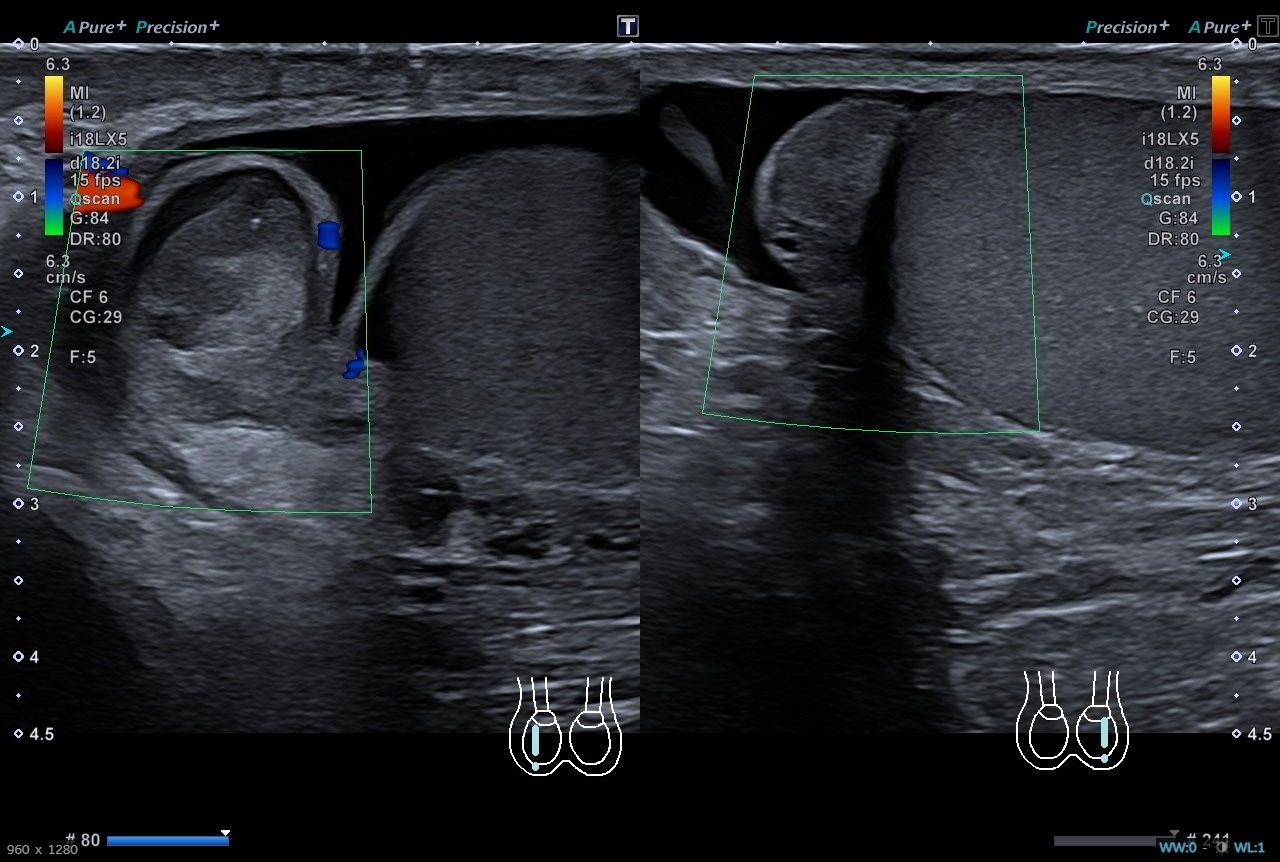

Pruebas complementarias: Sistemático de orina negativo. Ecografía escrotal: Testículos, epidídimos y cordones espermáticos de tamaño, morfología y ecogenicidad normales. Doppler normal en ambos testículos. Adyacente al polo superior del testículo derecho se identifica una estructura redondeada de unos 13 x 12 mms de ecogenicidad heterogénea, sin captación Doppler interna. Es sugestivo de torsión de hidátide de Morgagni, a correlacionar con evolución clínica. No hay datos de torsión testicular. Presencia de moderado hidrocele de aspecto reactivo.

El dolor testicular, es una patología prevalente en urgencias, en la cual hay que descartar una torsión testicular, debido a que es una situación de emergencia, tiempo dependiente, en el que se requerirá una cirugía de emergencia para poder salvar al testículo. De ahí la importancia del correcto diagnóstico diferencial y la realización de una ecografía que confirme o descarte nuestras sospechas.